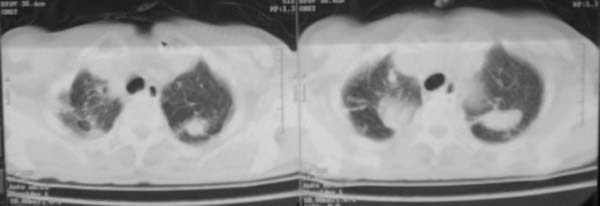

女,78岁,声嘶月余,否认有既往病史,有粉尘接触史10年。

多考虑尘肺,肿瘤性病变不除外

尘肺合并肺癌。

双上肺结节融合影,周围有纤维条索影,结合粉尘接触史,首先考虑尘肺。双侧颈部有增大淋巴结,有声嘶表现,肺癌淋巴结转移不能排除。可结合颈部淋巴结活检。